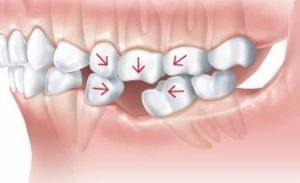

- Missing Tooth - There is always a chance when you lose a tooth due to oral diseases including tooth decay, gum diseases or cracked tooth. Some people do not have all permanent teeth. A missing tooth can cause severe complications to one's chewing, smiling and the health of other teeth. - What can you do*? - *Please consult your dental practitioner to discuss available options. Options are dependant on each individual's oral environment.  - Option 1 - Do nothing - Pros: - No cost involved

- Cons: - Teeth drifting

- Over-eruption

- Imbalanced load distribution

- Food impaction

- Compromised bone support